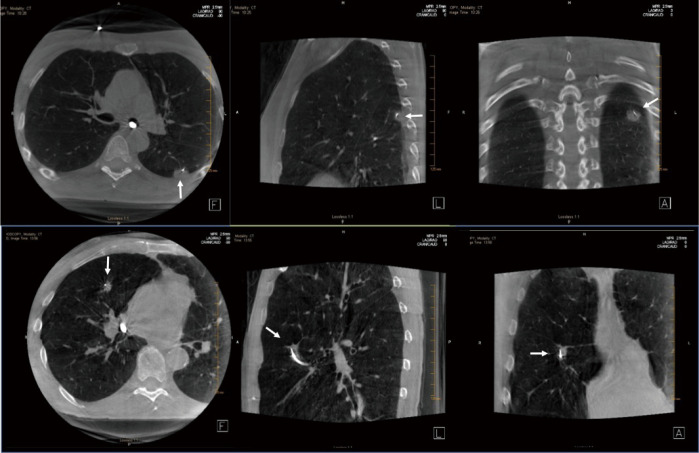

Figure 1.

Cone beam computed tomography (CBCT) images providing real time 3D confirmation of biopsy tool in contact with lung lesion. Top row shows a left lower lobe 1.4 cm lung nodule abutting the posterior pleural surface, which was positive for squamous cell carcinoma. Bottom row shows a right middle lobe 1.3 cm speculated lung nodule abutting the major fissure, positive for adenocarcinoma.

Recent studies have shown that CBCT can be used to confirm tool-in-lesion prior to biopsy with high confidence, with the potential to improve diagnostic yield (Figures 1,5) (6-10). For tool-in-lesion confirmation, CBCT is performed after the bronchoscopic biopsy tool is thought to have reached the target lesion, immediately prior to biopsy. The bronchoscope is secured and CBCT is performed; the resulting images are reviewed as MPRs or thick MIPs in multiple planes to determine the location of the tool relative to the lesion. In some clinical scenarios, reviewing the volume rendered images can be useful as well. Park et al. (10) found that tool-in-lesion confirmation by CBCT prior to biopsy was the only factor associated with increased diagnostic yield using a multivariate analysis in a single arm study of patients who underwent CBCT-guided transbronchial lung biopsy. A small prospective study conducted by Casal et al. reported a 25% increase in navigational success and a 20% increase in diagnostic yield attributed to the tool-in-lesion confirmation CBCT (6). In addition, an interesting finding of their study was the detection of atelectasis in CBCT that was not visible on fluoroscopy alone, which were producing false-positive RP-EBUS images and sometimes were completely obscuring the targets. These additional data further supported the utility of intra-procedural CBCT to accurately confirm tool-in-lesion during bronchoscopy for PPLS.